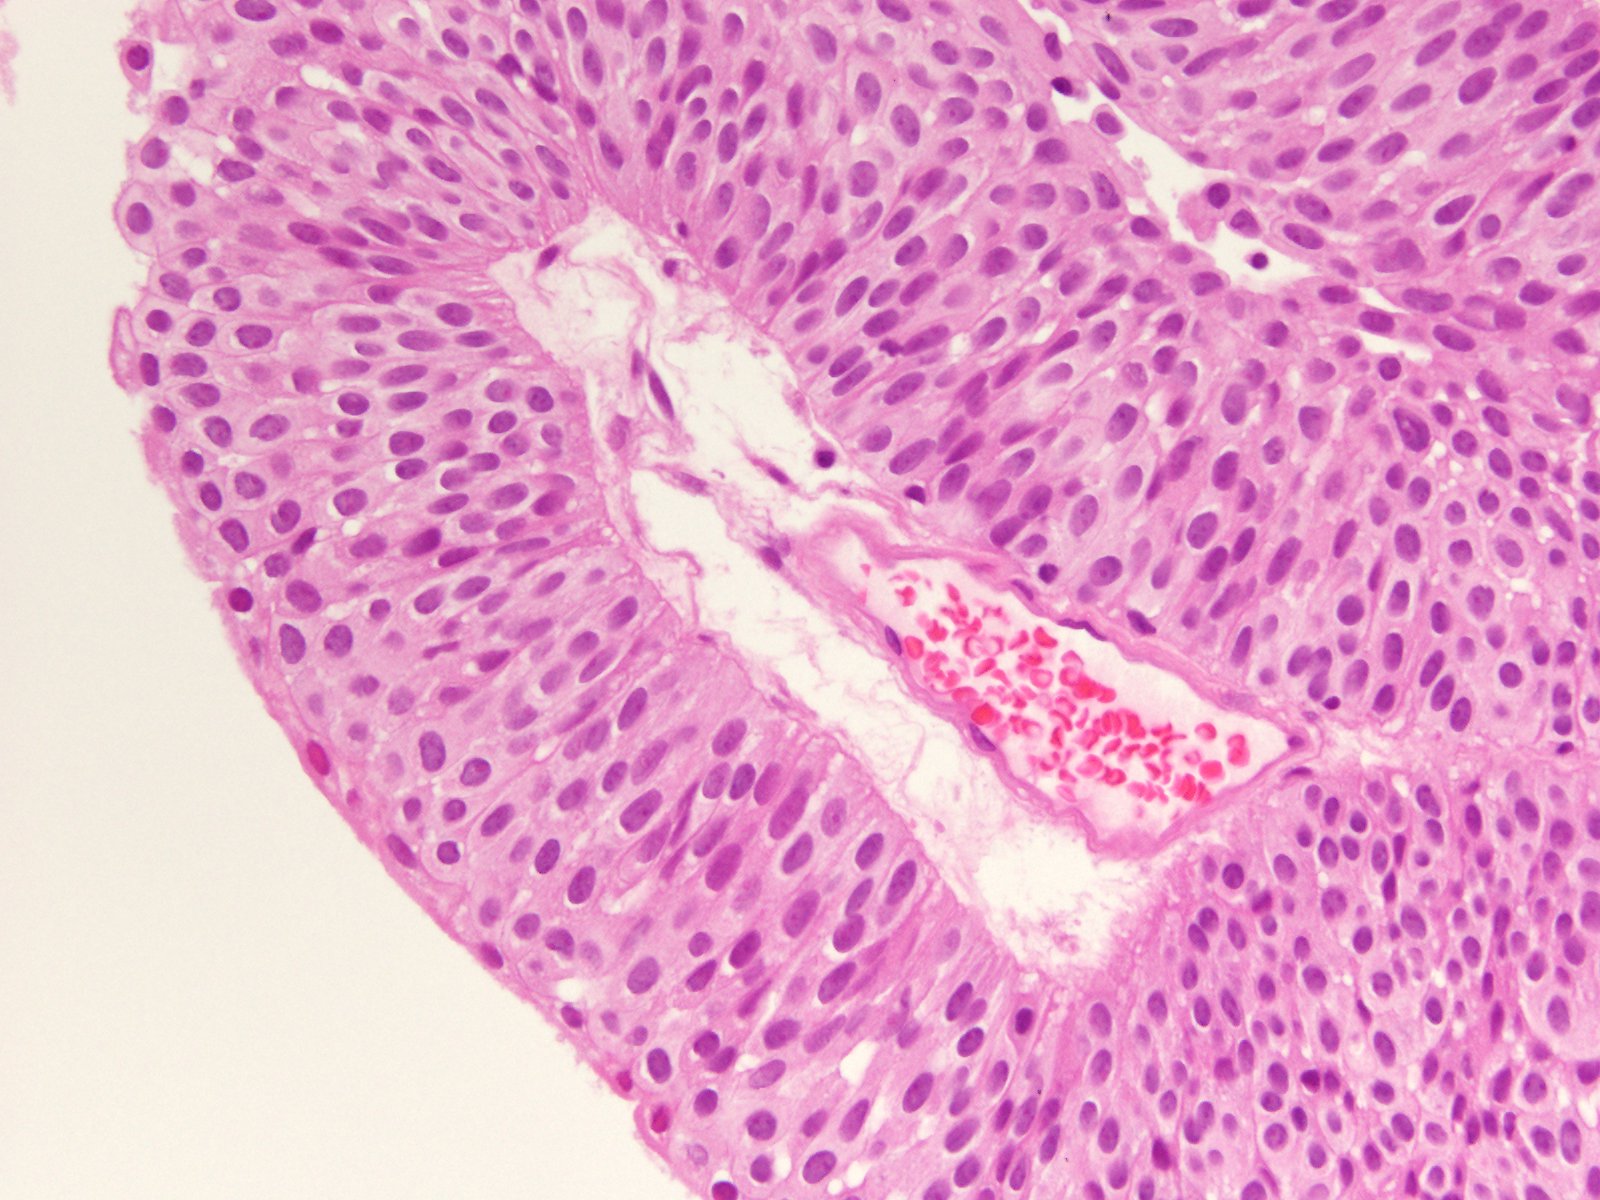

Consensus grade: Low-grade papillary urothelial carcinoma (LG-PUC)

would call it LG, but PUNLMP is an option. I thought there are too many layers to call it PUNLMP |

borderline between PUNLMP and LGPUC |

Case description (by case creator):

71 y/o, bladder tumor.